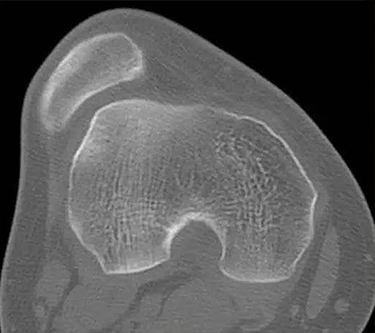

1、X线检查 对于习惯性髌骨脱位有很大的诊断价值。通常需拍膝关节的正侧位及髌骨轴位X线片,以显示髌骨的形态和位置是否正常。2、CT检查 可以更为准确的反映髌股关节情况。3、关节镜 其检查优势在于评估髌股关节软骨损害的程度,根据软骨损伤的程度决定手术方式。

根据临床表现和体征,结合X线、CT与关节镜检查通常均可明确诊断。